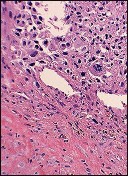

Question 4:

A 32-year-old female presents with progressive knee pain. Imaging reveals an eccentric, lytic epiphyseal-metaphyseal lesion of the distal femur. A biopsy demonstrates multinucleated giant cells in a background of mononuclear stromal cells. If neoadjuvant medical therapy is utilized prior to curettage, the mechanism of action of the most appropriate drug is:

Options:

- Direct cytotoxicity targeting multinucleated giant cells

- Inhibition of osteoclast proton pumps

- Inhibition of RANK ligand (RANKL)

- Inhibition of Vascular Endothelial Growth Factor (VEGF)

- Downregulation of parathyroid hormone receptors

Correct Answer: Inhibition of RANK ligand (RANKL)

Explanation:

The diagnosis is Giant Cell Tumor (GCT) of bone. Denosumab is a monoclonal antibody often used in the medical management of GCT. Its mechanism of action is the inhibition of RANK ligand (RANKL). In GCT, the neoplastic cells are the mononuclear stromal cells, which express RANKL. This recruits and activates the non-neoplastic, multinucleated osteoclast-like giant cells that cause the massive bone resorption.